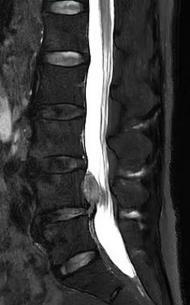

• 不同入路脊柱内镜手术治疗L4/5节段脱垂型腰椎间盘突出症的疗效比较

摘要:目的 观察经椎间孔入路内镜下腰椎间盘切除术(TELD)和经椎板间入路内镜下腰椎间盘摘除术(IELD)治疗L4/5节段脱垂型腰椎间盘突出症(LDH)的临床疗效。方法 回顾性分析2020年11月-2022年11月该院采用脊柱内镜手术治疗的75例L4/5节段脱垂型LDH患者的临床资料。根据手术入路的不同,将患者分为TELD组(53例)和IELD组(22例)。比较两组患者的手术情况和术后疗效。结果 与TELD组比较,IELD组的手术时间明显缩短,术中透视次数明显减少,差异均有统计学意义(P < 0.05);两组患者住院时间和并发症发生率比较,差异均无统计学意义(P > 0.05)。所有患者术后均获得12~19个月的随访。两组患者末次随访时的视觉模拟评分法(VAS)评分和Oswestry功能障碍指数(ODI)明显低于术前,且IELD组明显低于TELD组,差异均有统计学意义(P < 0.05)。按照突出物和神经根的不同位置进一步分析,两组肩上型患者(TELD组10例,IELD组6例)末次随访时的VAS评分和ODI明显低于术前,且IELD组末次随访时的VAS评分明显低于TELD组,差异均有统计学意义(P < 0.05);两组腋下型患者(TELD组8例,IELD组16例)末次随访时的VAS评分和ODI明显低于术前,且IELD组明显低于TELD组,差异均有统计学意义(P < 0.05);35例肩前型患者经TELD术后,末次随访时的VAS评分和ODI明显低于术前,差异有统计学意义(P < 0.05)。按照突出物的不同Lee分区进一步分析,两组Lee Ⅲ区患者(TELD组44例,IELD组10例)末次随访时的VAS评分和ODI明显低于术前,且IELD组的ODI明显低于TELD组,差异均有统计学意义(P < 0.05);两组Lee Ⅳ区患者(TELD组9例,IELD组12例)末次随访时的VAS评分和ODI明显低于术前,且IELD组明显低于TELD组,差异均有统计学意义(P < 0.05)。结论 采用TELD和IELD治疗L4/5节段脱垂型LDH,均可获得较满意的减压效果,但IELD的手术时间相对较短,X线透视次数较少,且对肩上型、腋下型、Lee Ⅲ区和Lee Ⅳ区的减压效果更有优势。